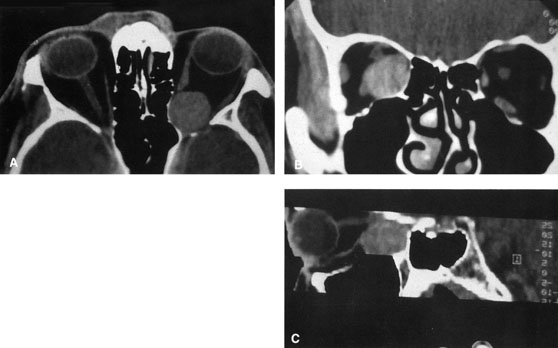

Valuable information about the nature and extent of an orbital pathologic process is provided by imaging studies such as computed tomography (CT) scan, magnetic resonance imaging (MRI), and orbital echography. Better spatial resolution, ready accessibility, and lower cost make CT the preferred choice for orbital imaging in most cases. Orbital fat provides a natural contrast between most adjacent orbital structures on CT scanning, and orbital bones are visualized well. Computed tomography is essential for evaluation of the orbital bones because they cannot be imaged with MRI. Direct coronal or sagittal images are important to identify the relationship of a lesion to the optic nerve so that the surgical approach can be planned to avoid traversing the optic nerve (Fig. 1).

Magnetic resonance imaging is useful in selected cases, especially when evaluating the orbital cranial junction. Significant bony artifact and a lack of orbital fat in the orbital apex make CT scan resolution of the orbital apex structures poor. Because cortical bone has low signal on MRI, there is no bone artifact when viewing the orbital apex on MRI. The lack of intervening fat in the apex to provide contrast is overcome on MRI because contrast is provided by the individual nuclear characteristics of each tissue so that the orbital apex structures are visualized well. Consequently, conditions that affect the optic nerve and chiasm, such as optic nerve meningioma and glioma, generally are evaluated with MRI rather than CT scan (Fig. 2).

Fig. 2. A. Axial orbital CT scan of right optic nerve meningioma. Note lack of detail in orbital apex. B. Axial orbital MR image, same patient. Note increased detail in orbital apex owing to lack of bone artifact. C. MRI with gadolinium contrast. Note extension into brain not easily appreciated with CT scanning or MRI without contrast.